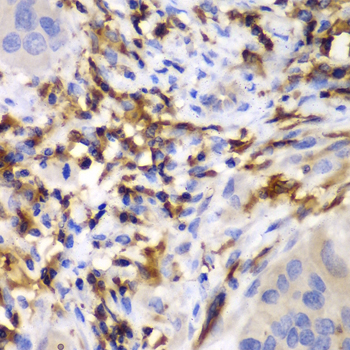

Immunohistochemistry of paraffin-embedded human liver cancer using HCLS1 antibody at dilution of 1:100 (400x lens).